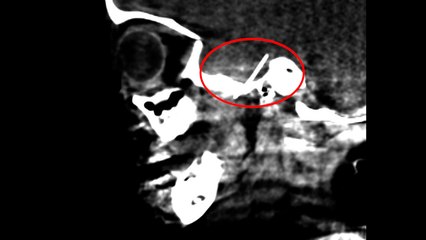

INSN Niño: Médicos intervienen con éxito a niña que tenía una aguja incrustada

La menor que vive en la provincia de Pataz, había acudido a una cita con el odontólogo pero en plena intervención hizo un mal movimiento.